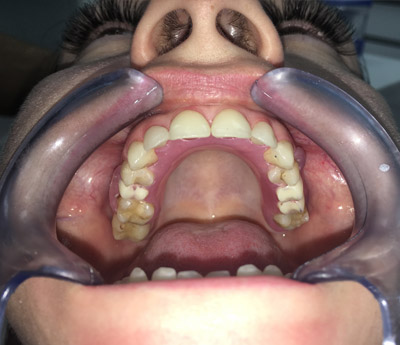

Un tale pezzo protesico ripristina l'integrità delle arcate dentarie. Una protesi mobile correttamente realizzata migliorerà esteticamente i lineamenti del viso del paziente, consentirà il ripristino della funzione masticatoria e migliorerà la fonazione.

Oltre al ripristino estetico della dentatura, il ponte dentale previene le complicazioni che possono derivare dalla mancanza di un dente. Una volta applicato, completerà il normale processo di masticazione e migliorerà la funzione fonetica.

Il sistema Fast&Fixed è un'alternativa immediata. Questa procedura ti permetterà di ritrovare il tuo sorriso in un unico intervento. Il risultato è immediato e recupererai autostima e fiducia in te stesso.